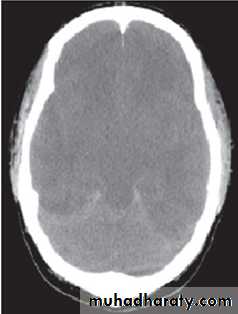

Cerebral Edema

• Cerebral edema is responsible for the majority of deaths related to DKA in children, and significant neurologic morbidity persists in many of the survivors.

• While it typically presents 4 to 12 hours after treatment is begun, it can present later, or earlier, including before treatment is initiated.

• The cause of cerebral edema in DKA is not known, but there are some risk factors attributed to cerebral edema. These include:

• young age.

• Rapid fluid replacement & insulin infusion.

• Injudicious use of bicarbonate therapy.

• Severe presentation:

• pH < 7.2

• lower serum bicarbonate concentration

• higher serum glucose concentration

• higher blood urea nitrogen concentration

• hypernatremia